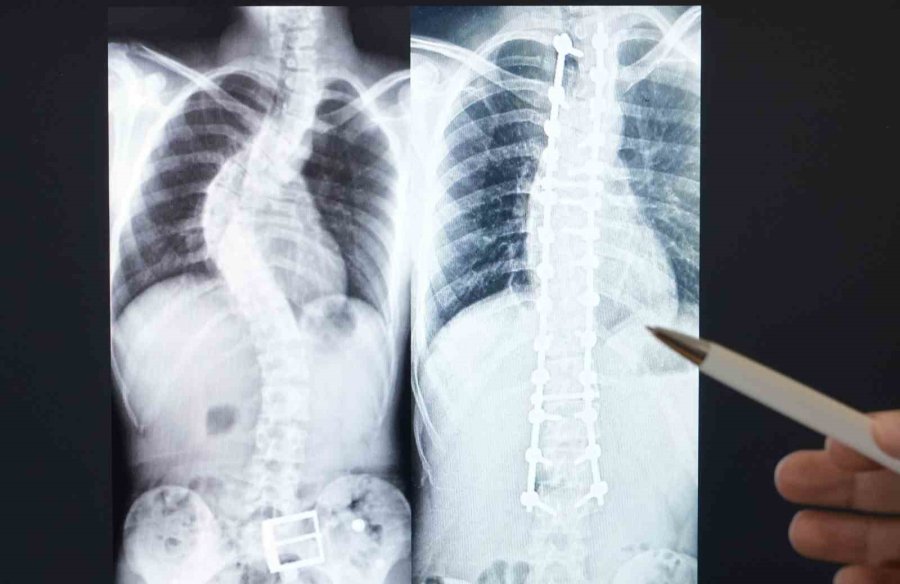

Skolyozun, omurganın önden bakıldığında eğriliğini ifade ettiği ve 10 derecenin üzerindeki eğriliklerin skolyoz olarak tanımlandığını söyleyen Bozduman, bu durumun genellikle duruş bozukluğu şeklinde belirti verdiğini açıkladı. Kız çocuklarında daha sık rastlanan bu durum, doğumsal faktörler, yaşlılıkta meydana gelen kırık, enfeksiyon, tümör veya kireçlenme gibi çeşitli nedenlerle de ortaya çıkabilir.

Bozduman, skolyozun tedavisinde egzersiz, fizik tedavi ve korse kullanımının önemli olduğunu, ileri durumlarda ise cerrahi müdahaleye başvurulabileceğini belirtti. Özellikle adolesan idiyopatik skolyozun, ergenlik döneminde kız çocuklarında sıkça görülen omurga eğriliği türü olduğunu ve erken tanının bu durumda çok önemli olduğunu vurguladı.

Ailelere yönelik tavsiyelerde bulunan Bozduman, çocukların fiziksel dengesine dair gözlemler yaparak, herhangi bir asimetri durumunda ortopedi ve travmatoloji uzmanına danışmaları gerektiğini söyledi. Ayrıca, skolyozun sıklığının binde 3 ile binde 7 arasında değişebildiğini ve genellikle her on hastadan birinin ameliyat gerektirecek durumda olduğunu ifade etti. Ameliyat ve takip süreçlerinde temel amaçlarının hastaların ameliyatsız bir şekilde problemlerini çözebilmek olduğunu belirtti.